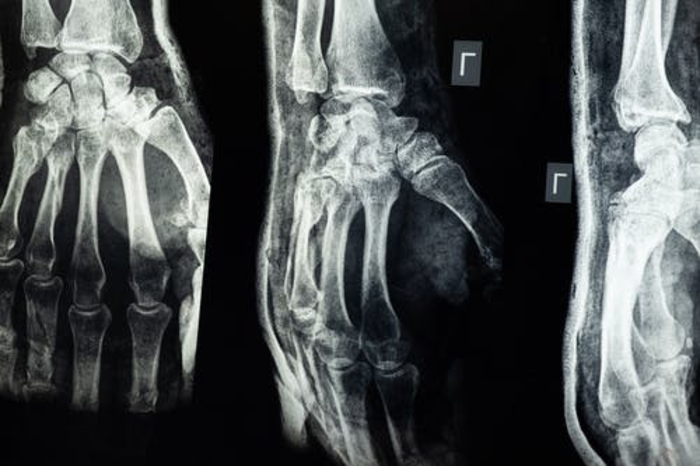

二、影像学表现

1.X线检查:是OA 明确临床诊断的“金标准”[3]

OA在X线片上的三大典型表现为:受累关节非对称性关节间隙变窄,软骨下骨硬化和(或)囊性变,关节边缘骨赘形成[3]。一些患者关节内可见游离体,甚至关节变形。